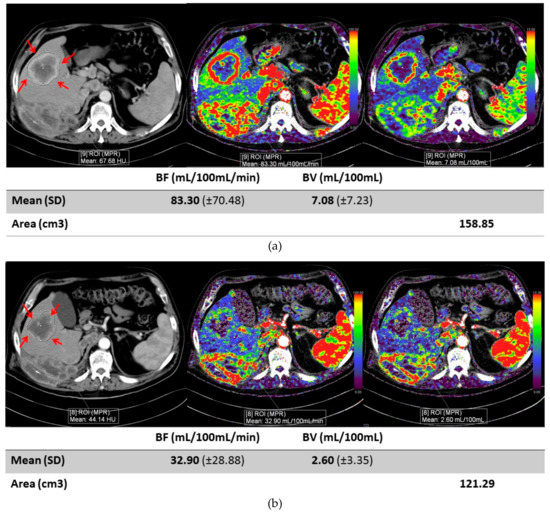

Early Changes in CT Perfusion Parameters: Primary Renal Carcinoma Versus Metastases After Treatment with Targeted Therapy

Cancers 2019, 11(5), 608; https://doi.org/10.3390/cancers11050608 - 30 Apr 2019

Computed tomography (CT) perfusion is a novel imaging method to determine tumor perfusion using a low-dose CT technique to measure iodine concentration at multiple time points. We determined if early changes in perfusion differ between primary renal tumors and metastatic tumor sites in [...] Read more.

Computed tomography (CT) perfusion is a novel imaging method to determine tumor perfusion using a low-dose CT technique to measure iodine concentration at multiple time points. We determined if early changes in perfusion differ between primary renal tumors and metastatic tumor sites in patients with renal cell carcinoma (RCC) receiving targeted anti-angiogenic therapy. A total of 10 patients with advanced RCC underwent a CT perfusion scan at treatment baseline and at one week after initiating treatment. Perfusion measurements included blood volume (BV), blood flow (BF), and flow extraction product (FEP) in a total of 13 lesions (six primary RCC tumors, seven RCC metastases). Changes between baseline and week 1 were compared between tumor locations: primary kidney tumors vs metastases. Metastatic lesions had a greater decrease in BF (average BF difference ± standard deviation (SD): −75.0 mL/100 mL/min ± 81) compared to primary kidney masses (−25.5 mL/100 mL/min ± 35). Metastatic tumors had a wider variation of change in BF, BV and FEP measures compared to primary renal tumors. Tumor diameters showed little change after one week, but early perfusion changes are evident, especially in metastatic lesions compared to primary lesions. Future studies are needed to determine if these changes can predict which patients are benefiting from targeted therapy. Full article